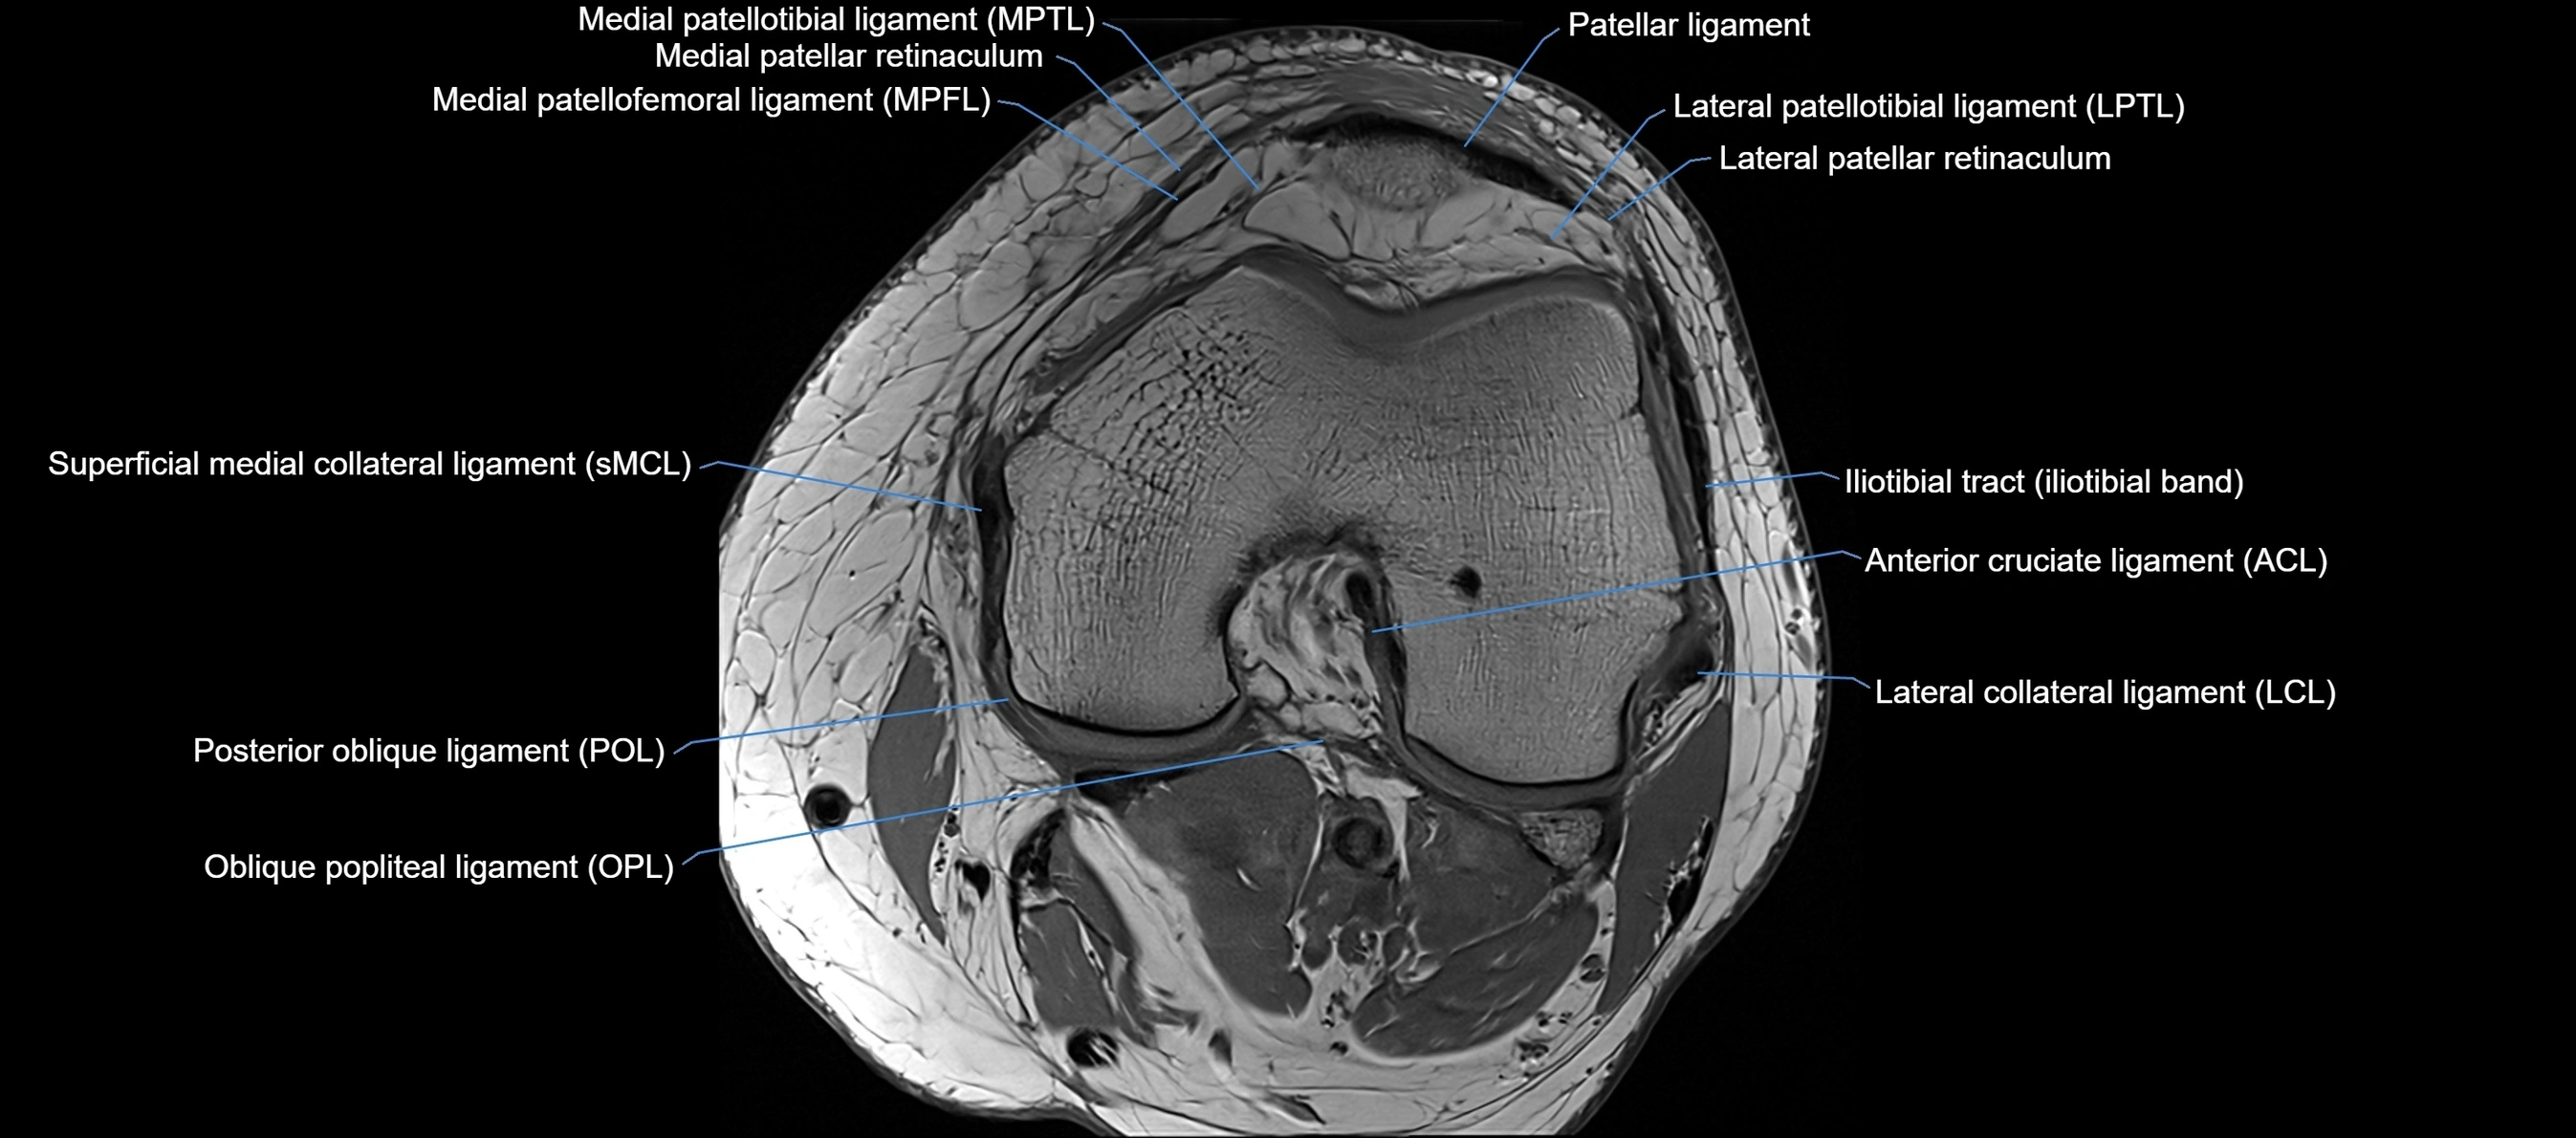

MRI images

image